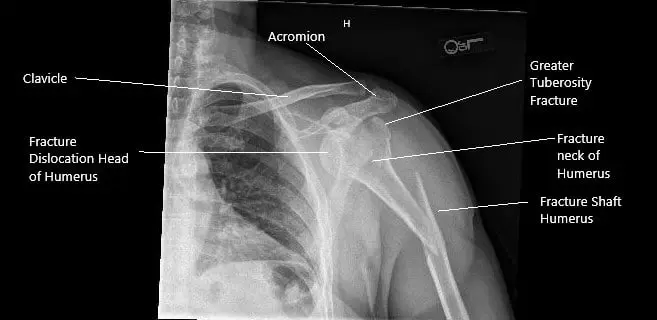

Pre-operative x-ray of the left shoulder in AP view.

The x-ray revealed a spiral fracture of the proximal shaft of the humerus with dorsal angulation at the fracture site. There was a fracture of the surgical neck of the humerus with a fracture of the greater tuberosity. A CT scan of the left shoulder revealed a comminuted left humeral head fracture with anterior inferior dislocation of the main fracture fragment including the humeral head.

A large comminuted fragment remains in the vicinity of the glenoid. A small linear fragment is noted between the humeral head and left scapula. There is a major separate fracture component of the proximal humeral diaphysis with inferior angulation.